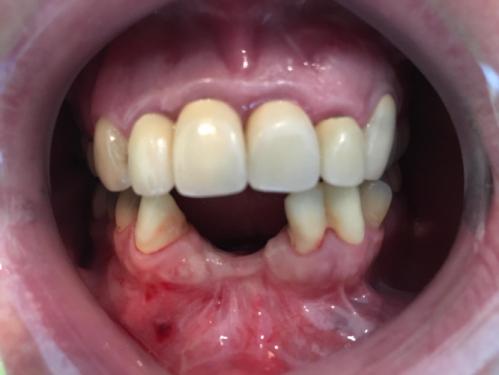

In unserer Praxis betreiben wir ein eigenes zahntechnisches Labor, in dem sich eine Zahntechnik-Meisterin und eine Zahntechnikerin mit großem Engagement um die Funktionalität und Ästhetik Ihres Zahnersatzes kümmern.

Die Vorteile liegen auf der Hand: Wir können schnell und in direkter Zusammenarbeit mit unseren Technikerinnen hochwertige Arbeiten anfertigen. Gerade bei der individuellen Farbgestaltung des Zahnersatzes profitieren Sie als Patient von der engen Zusammenarbeit.

- Ästhetische Kronen- und Brückenversorgungen